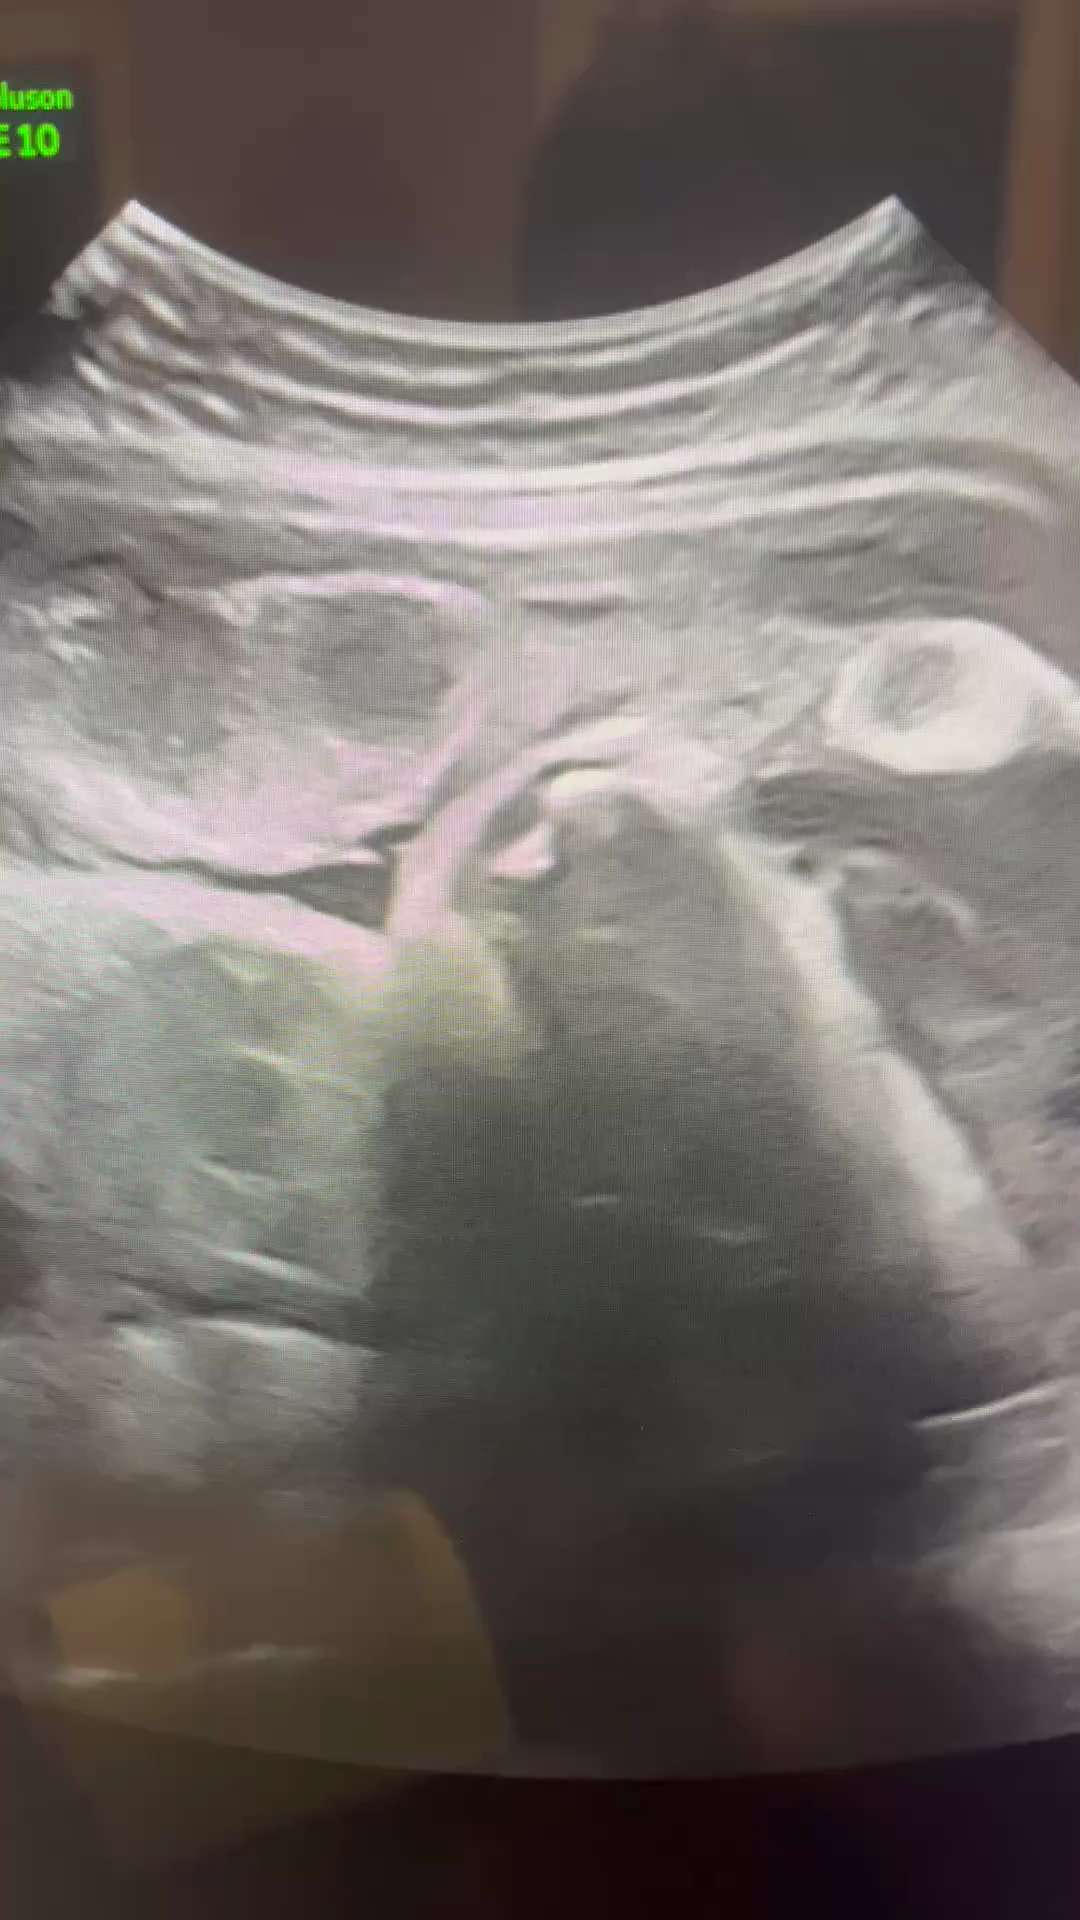

COVID19 Vaccines effects on placentas